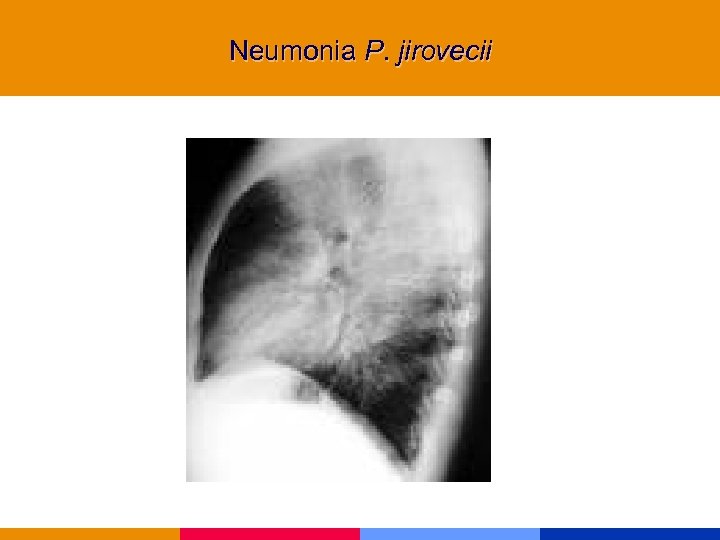

Neumonía por Pneumocistis jirovecii

Neumonía por Pneumocistis jirovecii

Neumonía por Pneumocistis jirovecii § CD 4 < 200 mm 3 § Comienzo insidioso: fiebre, tos seca, disnea. Hallazgos al examen físico incaracterísticos. § Lab: VSG: 50 mm. LDH, valor diagnóstico y pronóstico. Hipoxemia. § Rx infiltrado intersticial difuso, neumatocele, neumotórax. § TC de alta resolución.

Neumonía por Pneumocistis jirovecii § CD 4 < 200 mm 3 § Comienzo insidioso: fiebre, tos seca, disnea. Hallazgos al examen físico incaracterísticos. § Lab: VSG: 50 mm. LDH, valor diagnóstico y pronóstico. Hipoxemia. § Rx infiltrado intersticial difuso, neumatocele, neumotórax. § TC de alta resolución.

Neumonia P. jirovecii

Neumonia P. jirovecii

Neumonia P. jirovecii

Neumonia P. jirovecii

Neumonia P. jirovecii

Neumonia P. jirovecii

Neumonia P. jirovecii

Neumonia P. jirovecii

Neumonia P. jirovecii

Neumonia P. jirovecii

Neumonia P. jirovecii

Neumonia P. jirovecii

Neumonia P. jirovecii

Neumonia P. jirovecii